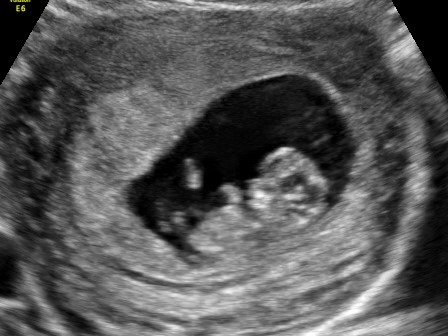

Småkjekset Skrevet 14. oktober 2016 Forfatter #191 Skrevet 14. oktober 2016 I dag var enig dagen hvor vi skulle få en snartitt på den lille hemmeligheten vår Jeg har vært ganske urolig i natt og slitt med søvnen for jeg var så nervøs for hvordan ting kunne være. Men det var helt uten grunn! Vi kom til en fantastisk behagelig jordmor som skulle stå for undersøkelsen. Fra jeg kom inn til jeg gikk følte jeg meg virkelig godt tatt vare på! Npr jeg la meg på benken var jeg småstressa for om jeg bare hadde innbilt med alt sammen, men idet hun begynte med undersøkelsen lyste det et lite knøtt mot oss Verdens herligste hjertelyd fikk vi høre, og tårene trilte hos mor Målingene hun tok var innenfor 9+6 og 10+3 som jeg har selv, så alt var i den skjønneste orden! Fikk med fire bilder hun skrev ut og en minnepenn hvor det er flere bilder og filmer Det er bare jeg og mannen som vet om dette enda, men han kjenner godt på følelsen av å slite med å holde det for seg selv Med E ventet vi til tidlig ul når jeg var 10+2 på vei, så sånn sett hadde det vært greit å fortelle det nå Vi hadde lyst å fortelle det til E i dag, men hun hadde ikke helt dagen når vi hentet henne i barnehagen, så vi får se om vi forteller henne i morgen

Småkjekset Skrevet 14. oktober 2016 Forfatter #197 Skrevet 14. oktober 2016 Legger med et aldri så lite bilde av knøttet også 2

A4-livet Skrevet 14. oktober 2016 #198 Skrevet 14. oktober 2016 Ååå, se på det fine lille mennesket da Blir gøy å høre hvordan reaksjonen TIL en blir. Jeg skjønte jo ikke jr noen ting (og gjør det nok ikke fortsatt) så her var det liksom ikke store reaksjonen....

Leviora Skrevet 14. oktober 2016 #199 Skrevet 14. oktober 2016 Ååh, så herlig! Og så fint bilde! Lykke til med å fortelle storesøster

Weebs Skrevet 15. oktober 2016 #200 Skrevet 15. oktober 2016 Wææ! Så fint bilde! Det er et lite menneske jo